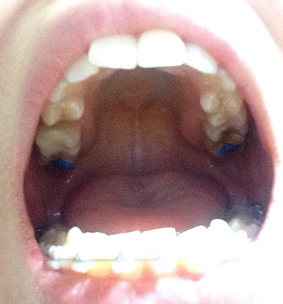

치아교정 장치를 부착후 상악에 바이트블럭 이라는것을 부착하였어요. 이것은 맞물림을 덜 되게 하는것인데 말인 즉슨. 원래 제가 입을 다물면 앞니와 아랫니가 많이 겹쳐지는 맞물림이깊은 교합인데 교정기를 달은채로 그대로 다물게 되면 앞니의 뒤쪽과 교정기기 충돌하기 때문에 이것을 방지하기 위한 장치가 바이트블럭이라고 할 수있어요~

상학의 어금니쪽에 딱딱한 블럭을 덧대어 치아가 완전히 맞물리지 않게 하여 치아와 교정기의 충돌을 막아 줍니다

사진을 보면 상악 위쪽에 파란색 부분이 보이시나요? 이것이 바이트블럭 이에요~